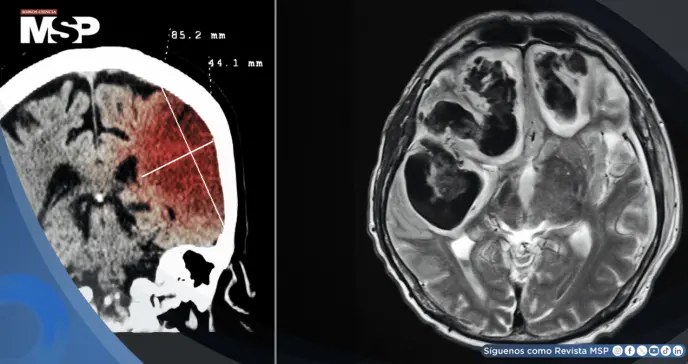

La tomografía computarizada (TC) es el estudio de elección para detectar sangrados. Se complementa con pruebas de coagulación, hemograma y control de glucosa. Si la TC inicial es negativa, pero se sospecha una hemorragia subaracnoidea, se puede realizar una punción lumbar.

Evacuación quirúrgica en hematomas cerebelosos > 3 cm o hematomas lobares que causan desplazamiento.